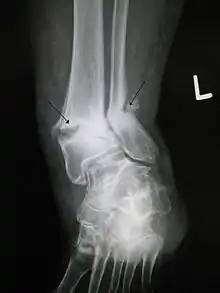

Fractures non-soudées, douleurs articulaires

Le mécanisme de l'ostéogenèse n'est pas clair. La thérapie PEMF revendique un certain avantage dans le traitement des fractures, mais avec des preuves issues d'essais randomisés « insuffisantes pour conclure à un bénéfice de la stimulation de la croissance osseuse » dans la pratique clinique actuelle du traitement des pseudarthroses et fractures aiguës[1]. Une revue systématique et méta-analyse récente suggèrent néanmoins que « PEMF ou LIPUS peuvent être bénéfiques dans le traitement des fractures aiguës (subissant un traitement non opératoire et les fractures aiguës du membre supérieur) en ce qui concerne le temps de consolidation radiologique et clinique »[1]. Une stimulation de la croissance osseuse PEMF ou LIPUS accélère aussi la consolidation de fractures diaphysaires aiguës[1].